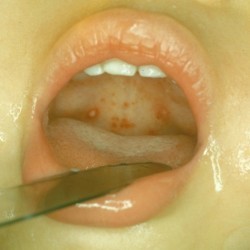

Отличить герпесную ангину у ребенка от других ее видов достаточно просто – на поверхности горла на 2-3 сутки появляются болезненные папулы ярко-красного цвета.

Из-за оттенка родителям кажется, что они наполнены кровью, но спустя сутк, окраска пузырьков меняется. В них отчетливо просматривается серозное содержимое прозрачного или белесого цвета.

Диаметр высыпаний может достигать 1-2 мм, а их количество варьируется от 6 до 12 штук. У детей с ослабленным иммунитетом болезнь протекает волнами, на третьи сутки к уже высыпавшим пузырькам могут добавиться еще 5-6 штук, а температура при этом повышается.

Слизистый эпителий гортани у малыша выглядит отечным и покрасневшим, с явными признаками воспаления. Боль в горле может быть интенсивной настолько, что ребенку тяжело есть и пить, а легкое прикосновение к язвочкам доставляет массу дискомфорта.

Каждая папула окружена ярко-красным венчиком, а серозное содержимое из нее выдавить невозможно, и нельзя пытаться этого делать. Через 3-4 дня пузырьки вскроются самостоятельно, а корки и эрозии заживут.

На мягком нёбе наблюдаются везикулы (пузырьки)

На слизистой оболочке мягкого нёба может отмечаться вирусная энантема (мелкоточечная сыпь ярко-красного цвета). На нёбных миндалинах и задней стенке глотки характерным признаком будет наличие везикул (пузырьков) с прозрачным содержимым внутри.

Сыпь представляет собой мелкие пузырьки, наполненные серозной жидкостью. Через некоторое время они лопаются, происходит их слияние, что приводит к образованию язвочек, покрытых плёнкой. Благодаря таким признакам диагностика заболевания становится более точной.